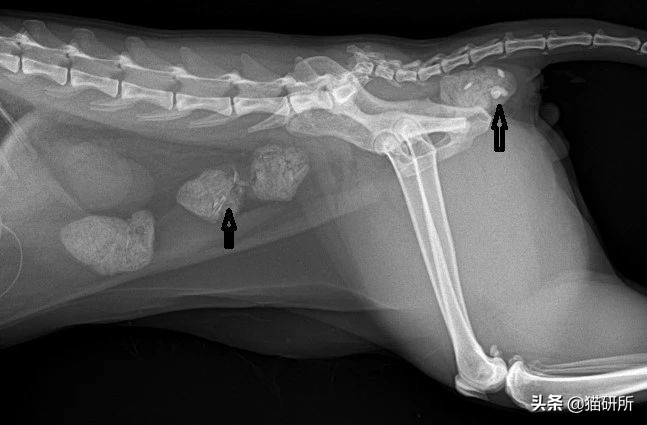

❗ 一例肠道异物引发的猫咪便秘

高密度影像(箭头)为玩具碎屑@姜医生提供